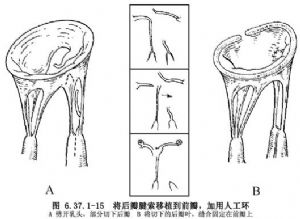

①腱索断裂:后瓣腱索断裂,受累的瓣叶<后瓣的1/3者可矩形切除瓣叶,边缘缝合,对应的瓣环做折叠(图6.37.1-12),也可用瓣叶滑行方法(图6.37.1-13)。前瓣腱索断裂,常用的方法有:一级腱索断裂,将瓣叶边缘固定在二级腱索上(图6.37.1-14)。此方法要有1或2根较厚和结实的第2级腱索。先在断裂的腱索上缝2或3针,然后缝至二级腱索上打结;腱索移植用于前瓣腱索断裂,把与之相对应的带腱索的后瓣切下,乳头肌劈开,将切下的后瓣固定在前瓣叶上。后瓣叶对缘缝合,瓣环折叠(图6.37.1-15);三角形切除,在腱索断裂的瓣叶处做窄的等边三角形切除,通常不超过1.5cm。